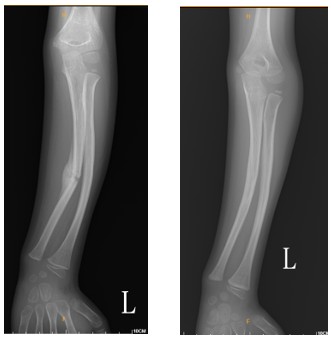

兒童的骨骼與成人堅硬的骨質相比,兒童骨骼較柔軟有彈性。因骨質尚未完全鈣化,較小的外力就可能造成骨骼彎曲或骨折。根據研究顯示,在18歲以前,約有50%的男孩與30%的女孩會經歷至少一次骨折。幸運的是,相較於成人骨折往往需3~6個月癒合,兒童通常僅需4~6週即可癒合,且石膏固定時間也大多在3~6週內,顯示出兒童骨骼強大的修復與塑形能力[圖一]。兒童骨骼骨膜較厚、含豐富膠原蛋白,這些都是促進癒合的有利條件。不過,兒童骨骼兩端存在尚未閉合的「生長板」,這是控制骨骼長度與形狀的重要部位。一旦生長板受損,可能造成骨骼彎曲、手腳長短或關節變形等後遺症。因此,若懷疑骨折波及生長板,需由專業醫師詳細評估與追蹤治療,以確保孩子未來的正常發育。

圖一 8歲男童左前臂尺橈骨折石膏復位治療一年後塑形結果